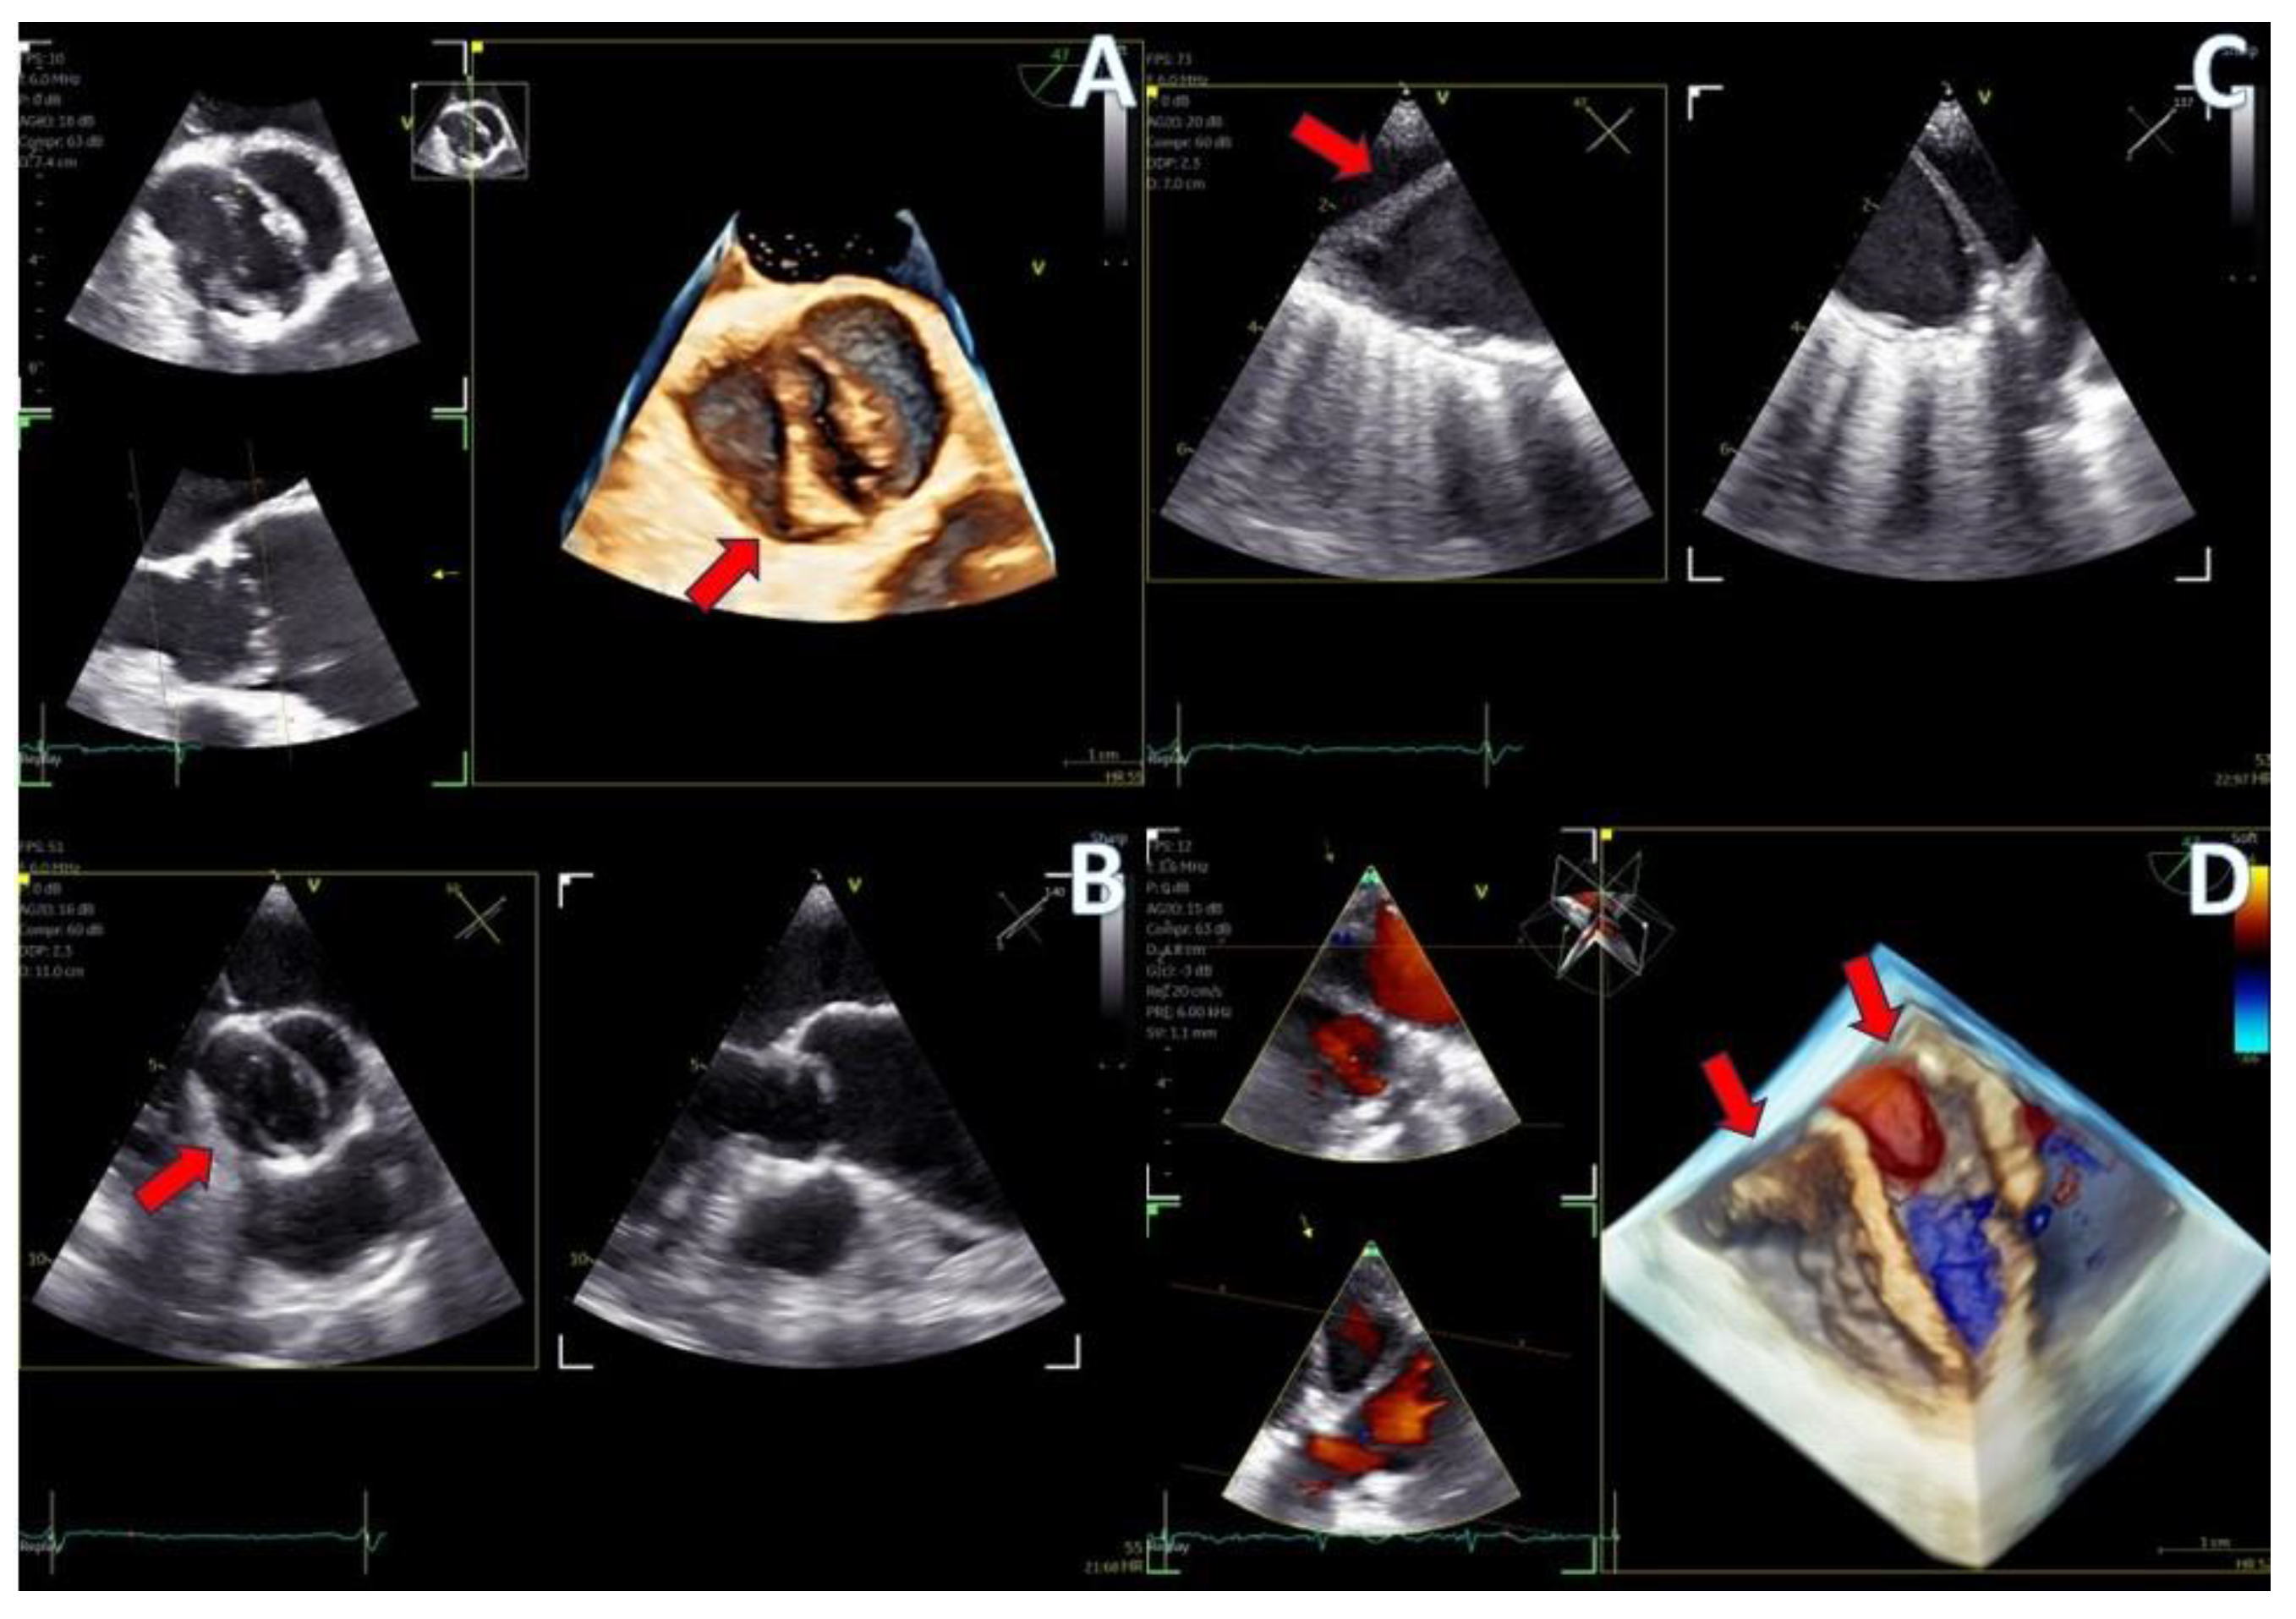

Figure 7.

Secundum ASD closure case; (A) Flexislice method for measurements with both 2D and 4D images, (B) guide catheter through the defect (red arrow), (C) biplane 2D images showing the implanted ASD occluder, (D) 3D volume-−rendered image showing the final result with an ASD occluder.

Figure 8.

LAA closure case; (A) biplane images of the LAA showing the presence of distal thrombus (red arrow), (B) measurements of the ostium and the landing zone with biplane imaging, (C) Biplane images of the implanted AMULET device (red arrow), (D) 3D volume−rendered image showing a view of the implanted AMULET device (red arrow).

Figure 9.

PFO closure case; (A) J wire through the PFO tunnel (red arrow), (B) stiff wire for guidance through the PFO tunnel (red arrow), (C) 3D volume−rendered view of the guide catheter through the PFO tunnel (red arrow), (D) final result with left atrial view of the PFO Amplatzer occluder (red arrow).

In the case of LAA closure (Figure 8, video S3), 3D tools (MPR-flexislice) aided in accurate sizing of the ostium and the landing zone (important for AMULET device), particularly in the presence of distal thrombus where contrast infusion was contraindicated. The final result was satisfactory, with no leakage observed and a stable device placement was confirmed with a tug test.

PFO closure cases (Figure 9, video S2) benefited from the probe’s excellent imaging, enabling precise wire insertion and providing anatomical criteria for device sizing. A bubble contrast study was performed at the beginning and at the end of the procedure for any remaining shunt. The stability of the device was confirmed with a wiggle test. Similarly, in the ASD case (Figure 7, video S1), the probe facilitated visualization of all defect rims and accurate sizing of the oval-shaped defect (with MPR) confirmed with balloon sizing and stop-flow technique and ensured a successful outcome with no residual shunt observed.

The imaging capabilities of the 4D mini-TEE probe were consistently excellent across all procedures (Figure 5, Figure 6, Figure 7, Figure 8 and Figure 9). Trans-septal puncture in ablation cases was facilitated by biplane imaging (Figure 5), demonstrating a nice tending of the septum. For the guidance of wires to the pulmonary veins, both 2D and 4D volume-rendered images were utilized (Figure 5 and Figure 6), expediting the procedure. The TEE probe was removed after the insertion of the cryo-ablation catheter into the LA.